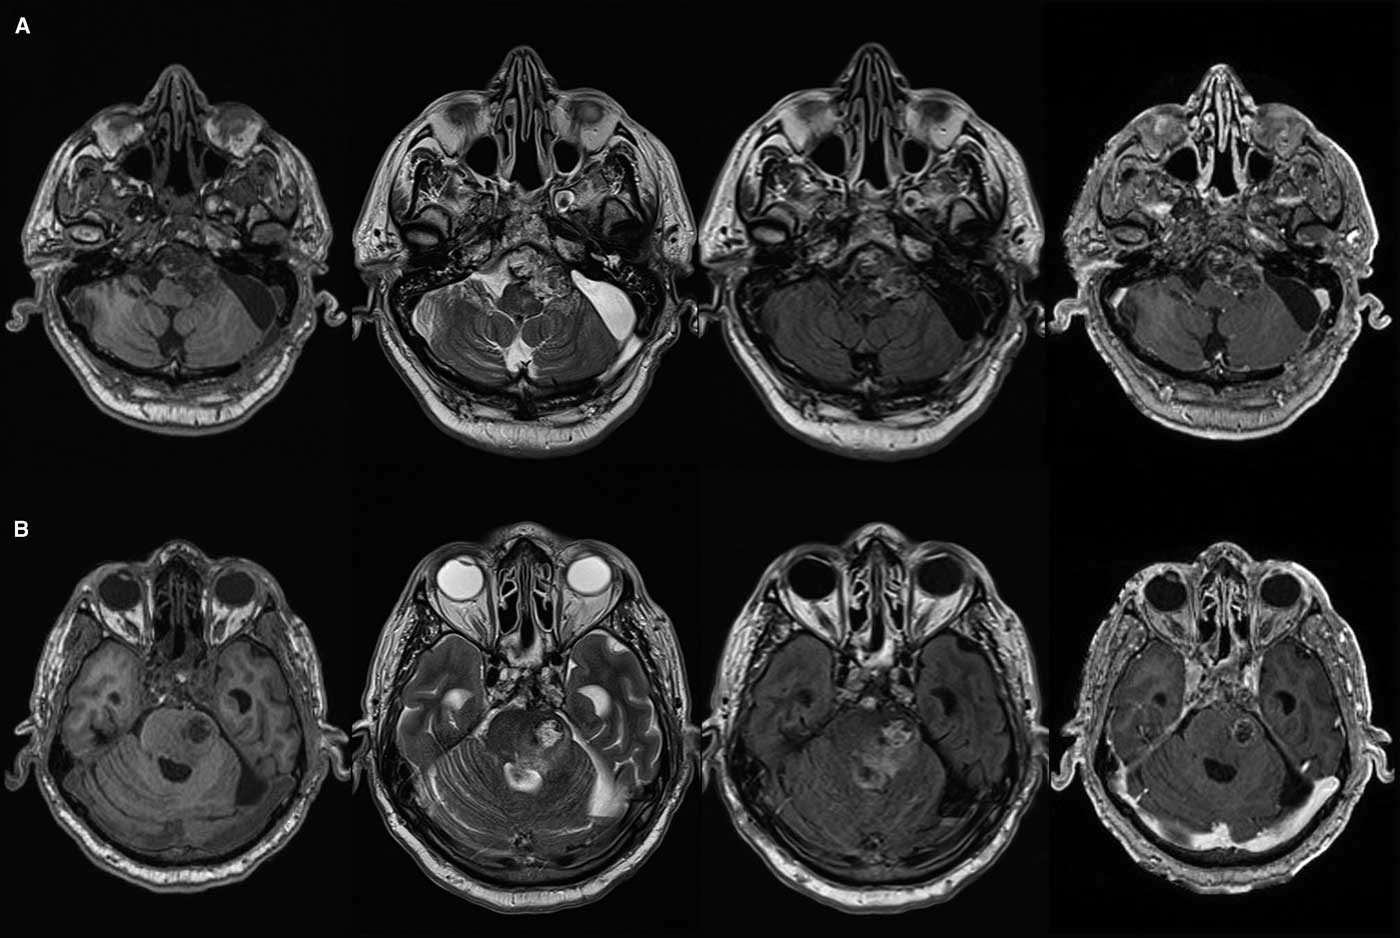

The patient remained free of recurrence until 1 year after his third operation. At that time radiologic recurrence was noted with only minor symptoms. After 6 months, the patient developed lower cranial nerve deficits including swallowing issues and drop attacks. An attempt at surgical decompression was undertaken via a retrosigmoidal approach, but the tumor had become too adherent to the brainstem, extending from the prepontine cistern into the belly of the pons with cystic component (Figure 1), with adjacent signal changes on FLAIR and T2 images. Diffusion weighted imaging showed some areas of restriction suggestive of infarction. The patient passed away during admission, likely from brainstem perforator infarct (Figures 2-4).

Figure 2 Axial T1, T2, FLAIR and post-gadolinium T1 magnetic resonance images showing clival chordoma and T2/FLAIR signal change in prepontine cistern (A) with intrapontine invasion (B).